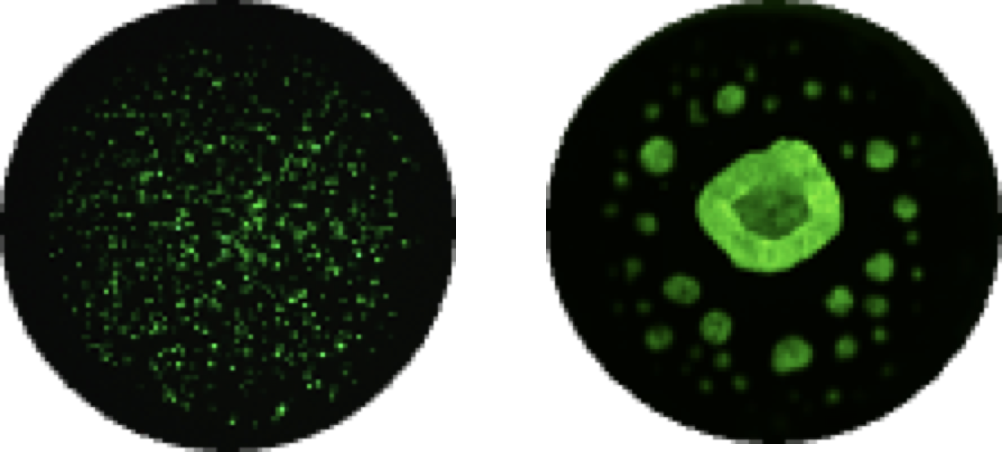

고속 자동화 분주 장비 (ASFA® Spotter)와 384 Pillar plate를 이용하여 적은 양의 검체로 검사 가능

공초점 현미경과 비교하면 100배 이상 빠른 스캔이 가능한 light sheet 형광 현미경을 이용해서 최적의 항암화학제/표적치료제 결정합니다.